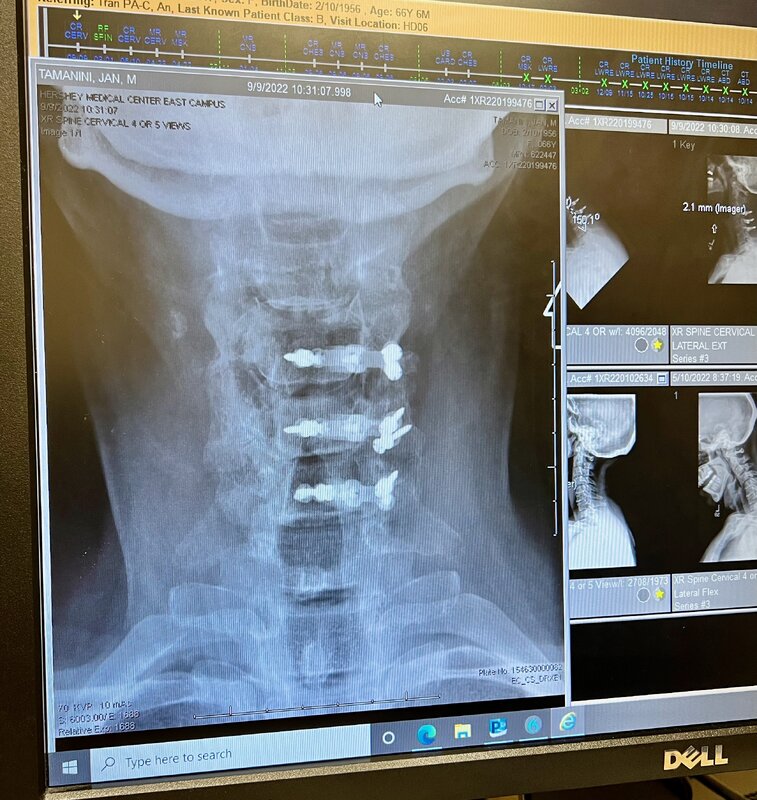

Pete, so sorry to hear! You might recall from Coz that I was deferring spine surgery until after the trip. Is your 2 to 5 cervical, thoraxic, or lumbar? I had partial laminectomies on C3 and C7, and laminoplasties on C4-6 (postop xray photo attached)

I felt better waking up in recovery after the surgery than I had in almost a year! Recovery went relatively smoothly, and with PT I was back to good form (and cleared for diving) in a few months! If you have any questions about it, PM me and I'll be happy to answer.